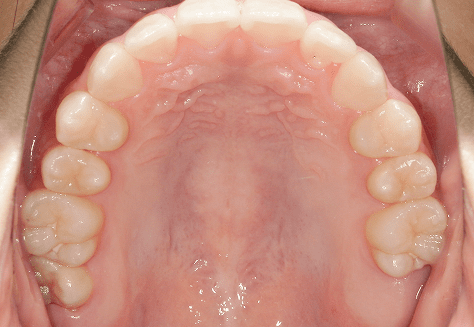

S.K

治療前

治療後

主訴

歯が重なっていて気になる。前歯が出ていて唇が閉じにくい。ハミガキがしにくい。

診断

上顎前突・叢生

年齢/性別

20代/男性

抜歯部位

上下第三大臼歯

使用装置

上下インビザライン

保定装置

上下ビベラリテーナー

料金

初回資料採得・・・・・・・30,000円

診断料・・・・・・・・・・33,000円

動的治療終了時資料採得・・5,500円 -

基本料金

990,000円

診察料金

1,100円×33回

治療期間

3年5カ月